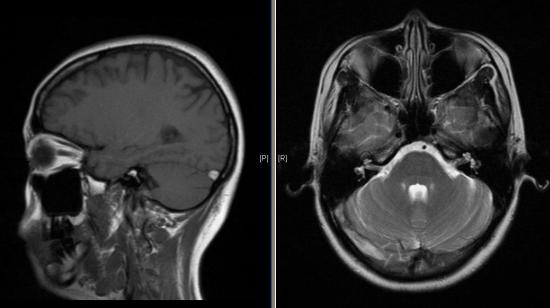

Էնցեֆալոպաթիայի կլինիկային բնորոշ են տարբեր նյարդաբանական խանգարումներ’ հիպերկինեզներ (խորեատիկ և ատերոիդ), ստորին վերջույթների հիպերտոնիա և վերին վերջույթների հիպոտոնիա՝ օրալ ավտոմատիզմների ախտանիշներ (կնճիթային ռեֆլեքս), նիստագմ, պտոզ, ինչպես նաև՝ միոզ, անիզոկարիա, կոնվերգենցիայի և լույսի ռեակցիայի թուլացում (Ջուդենի ախտանիշ)։ Սովորաբար, լինում են պոլինևրիտներ, պարեզներ և մենինգեալ նշաններ։